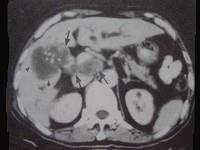

问题 男,68岁,上腹部隐痛二月余,CT检查如图,最可能的诊断是 ( )

选项 A、胆囊息肉 B、胆囊区转移瘤 C、胆囊癌(肿块型) D、胆囊腺肌增生症 E、慢性胆囊炎

答案 C